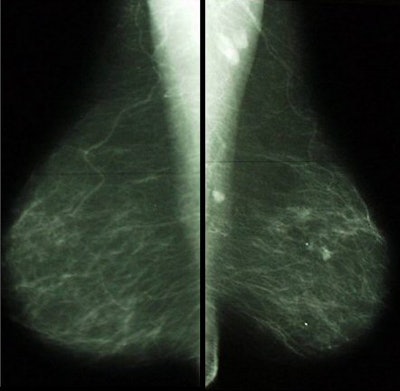

![]() |

| Note the black triangular area in the region of the IMF on the left MLO view. The IMF is not open on this image. With digital technology we can see the skin line in this area and it is more obvious. Images courtesy of Tammy Coryell. |